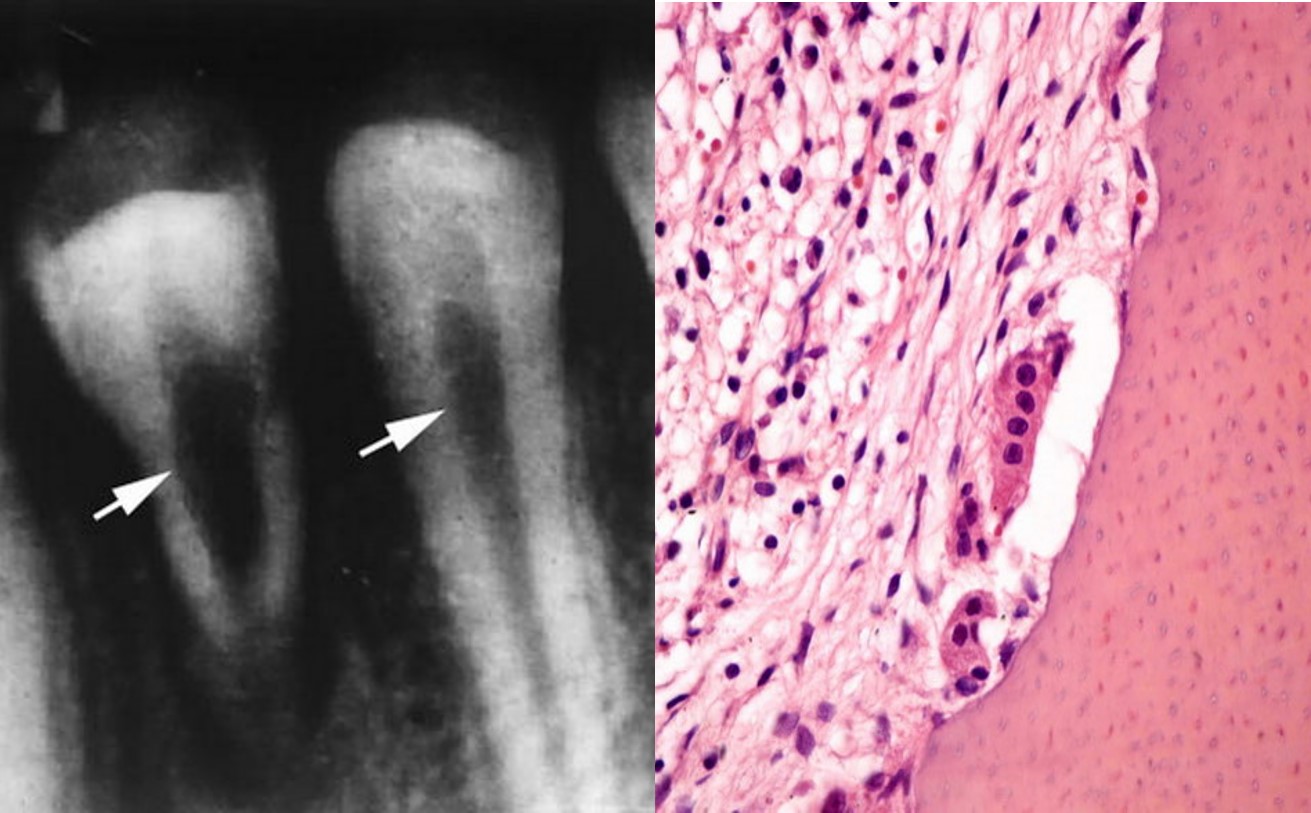

2)病理变化

a.牙髓部分或全部被炎性肉芽组织所取代;

b.牙髓腔面牙本质不规则吸收,凹陷内可见破骨细胞(图8.3-1)。

图8.3-1 牙内吸收